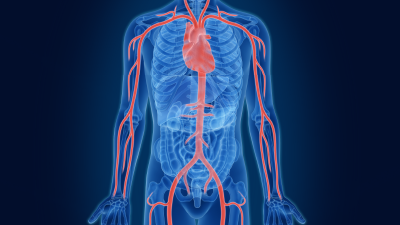

Heart

Watch the video to view Mass General's performance for procedures to treat conditions of the heart.

Vessels

Watch the video to view Mass General's performance for procedures to treat vascular conditions.